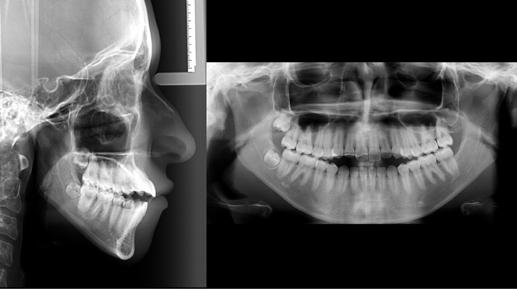

A 10 éves férfi páciens a felső frontfogai késői/nem megvalósuló előtörése miatt kereste fel a rendelőnket. A klinikai és a radiológiai vizsgálat során a jobb felső nagymetszőfog impakcióját észleltük (1. ábra). A fog horizontális tengelyállással és dilacerált gyökérrel rendelkezett. A felső dentális középvonal a fogak vándorlása miatt jelentős mértékben elcsúszott. A bal felső kismetszőfog is rendkívül kedvezőtlen pozícióba került.

Dr. Kazem Dalaie, dr. Samin Ghaffari, dr. Mazir Mir (Irán, Németország) 1. a ábra: Az intraorális felvételen jól látható a jobb felső nagymetszőfog lehetséges impakciójára utaló foghiány.

1. b ábra: A panoráma röntgenfelvételen megfigyelhető a teljes impakcióban lévő jobb felső nagymetszőfog. 1. c ábra: A CBCT felvétel is igazolja a jobb felső nagymetszőfog impakcióját.